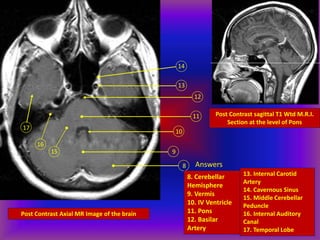

Post Contrast Axial MR Image of the brain

Post Contrast sagittal T1 Wtd M.R.I.

Section at the level of Pons

Answers

8. Cerebellar

Hemisphere

9. Vermis

10. IV Ventricle

11. Pons

12. Basilar

Artery

13. Internal Carotid

14. Cavernous Sinus

15. Middle Cerebellar

Peduncle

16. Internal Auditory

Canal

17. Temporal Lobe